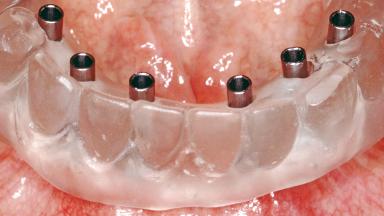

Conventional Loading of Six Implants in the Mandible and Final Restoration with a Full-Arch Metal-Ceramic FDP

# of Implants 6

Type of Implants One-Piece

Attachment One-Piece

Prosthesis Type FDP

Loading Protocol Conventional/early

Retention Screw-retained, with 4 or more splinted implants Screw-retained, with 4 or more splinted implants